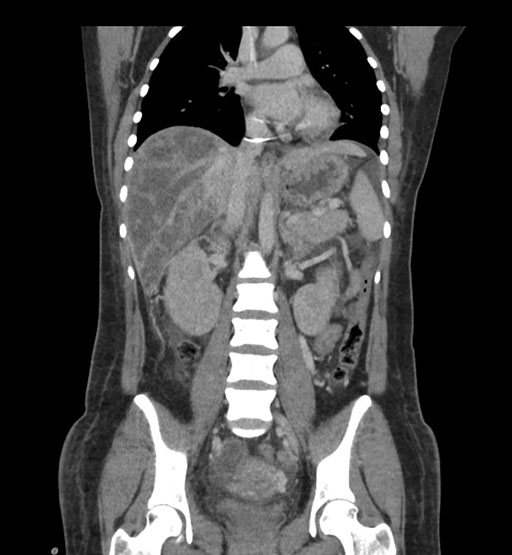

Look through the patient's CT scan to identify any areas of concern for the necessary procedure.

Coronal Arterial